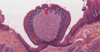

These are glands. Specifically they are the glands of Von Ebner - They secrete their product into the troughs on the sides of the circumvallate papillae.

tongue

Duct of mucous gland.